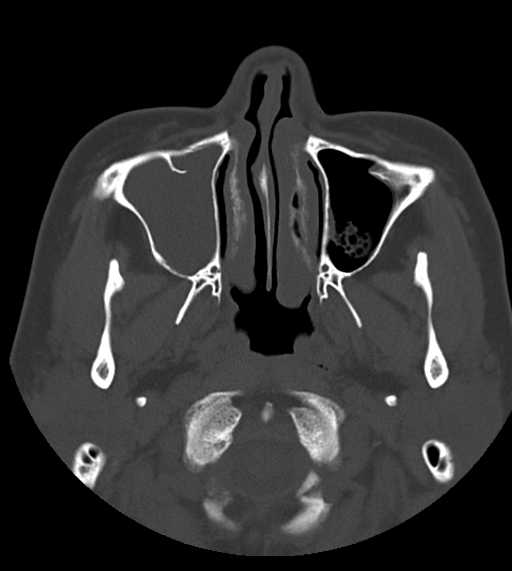

CT検査

内科領域

頭部

副鼻腔炎